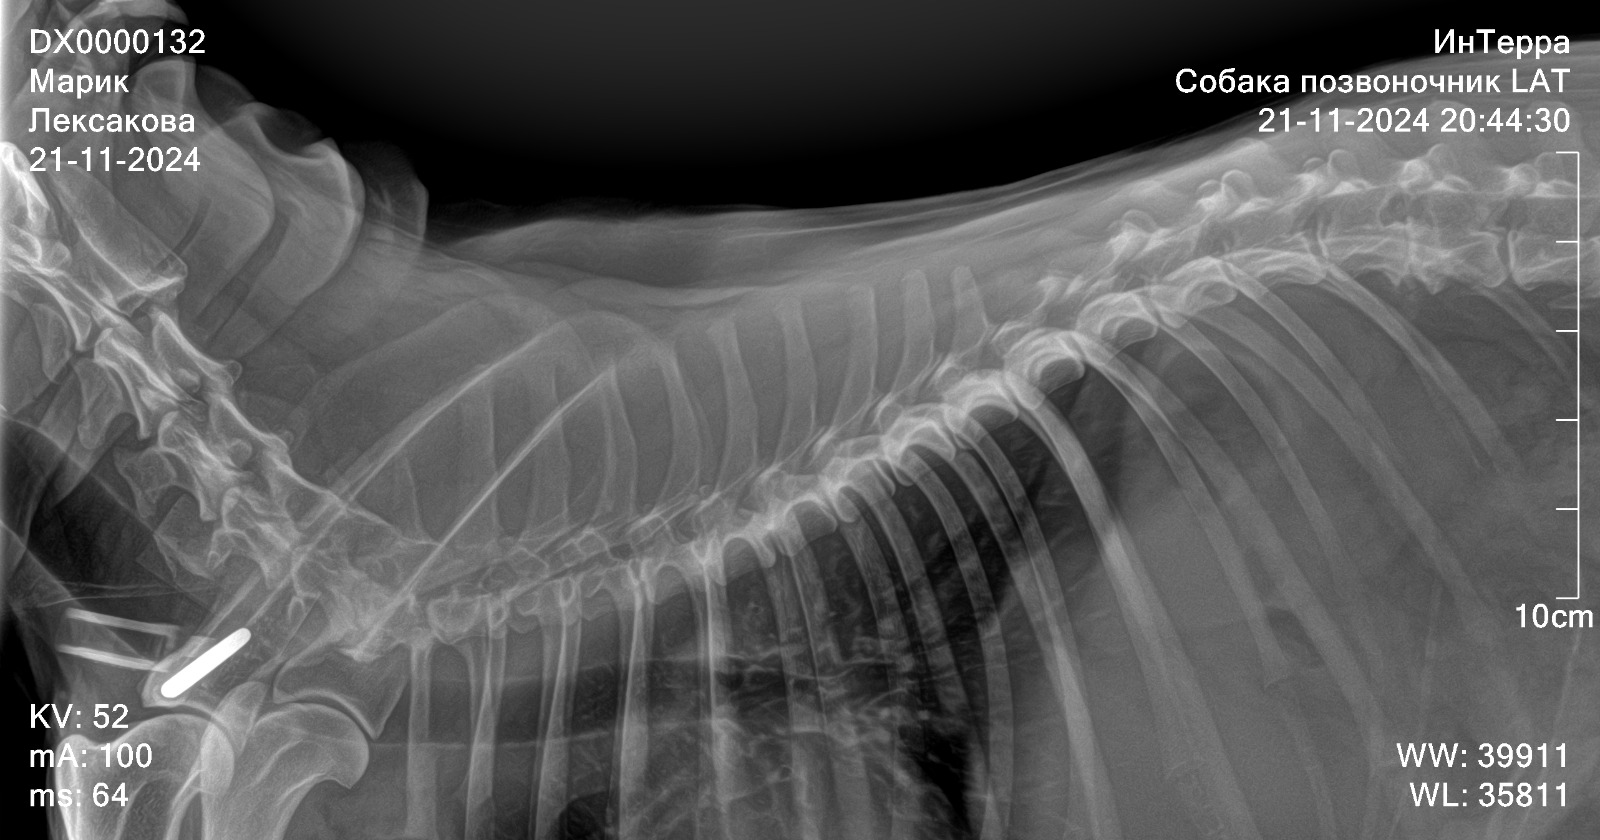

Рентген позвоночника

Вложения

IMG-20241121-WA0054.jpg

IMG-20241121-WA0047.jpg

IMG-20241121-WA0045.jpg

IMG-20241121-WA0034.jpg

IMG-20241121-WA0041.jpg